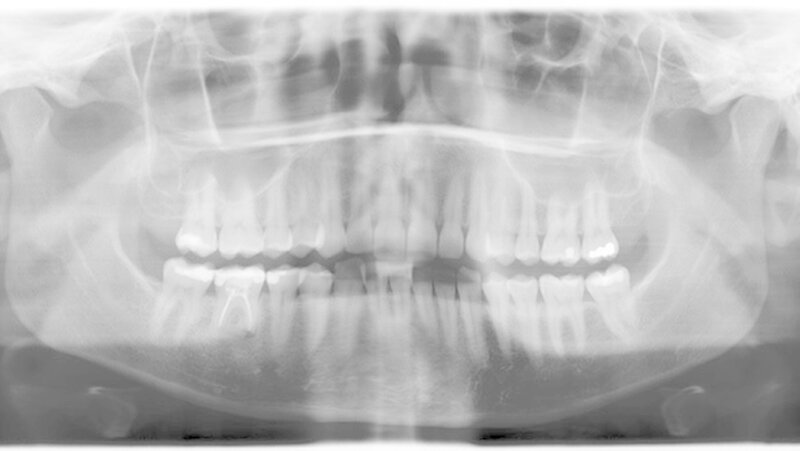

Bei kontinuierlich fehlender Pusabsonderung konnten die Drainageröhrchen am vierten postoperativen Tag entfernt werden. Die Patientin bemerkte zu diesem Zeitpunkt bereits eine leichte Besserung der Mundöffnung. Die zunächst aufgetretene Besserung stagnierte jedoch im ersten Monat bei etwa 2,2 cm SKD, so dass wir der Patientin Physiotherapie und tägliche Übung mit TheraBite® verordnet haben. Nach 20 physiotherapeutischen Behandlungen (dreimal wöchentlich) und dreimonatigen Übungen mit diesem Rehabilitationssystem zur Verbesserung der Mundöffnung kam es zu einer kompletten Wiederherstellung der Mundöffnung (Abbildung 4) und Kaufunktion.